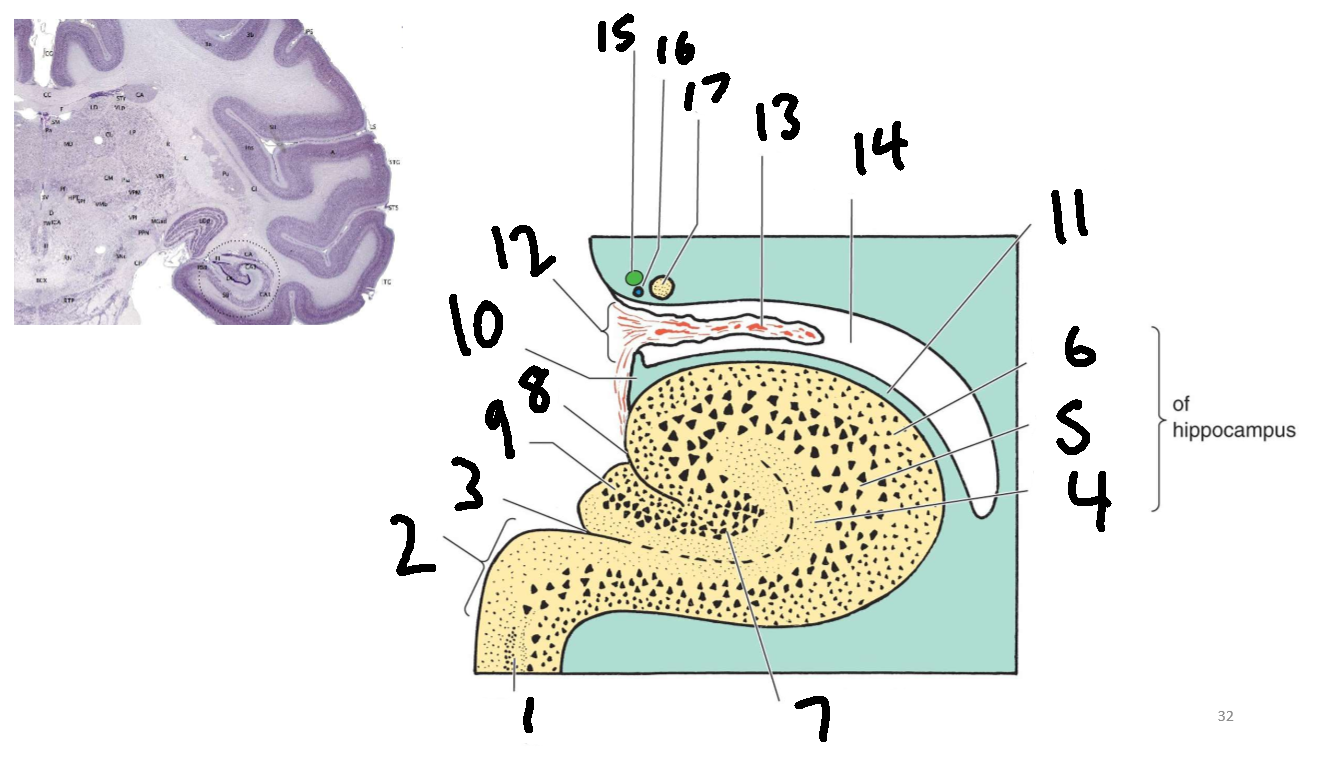

What is 1?

parahippocampal gyrus

What is 2?

subiculum

What is 3?

hippocampal sulcus

What is 4?

molecular layer

What is 5?

pyramidal layer

What is 6?

polymorphic cell layer

What is 7?

granule cell layer of dentate gyrus

What is 8?

fimbriodentate sulcus

What is 9?

dentate gyrus

What is 10?

fimbria of hippocampus

What is 11?

alveus

What is 12?

choroid fissure

What is 13?

choroid plexus

What is 14?

temporal horn of lateral ventricle

What is 15?

stria terminalis

What is 16?

thalamostriate vein

What is 17?

tail of caudate nucleus